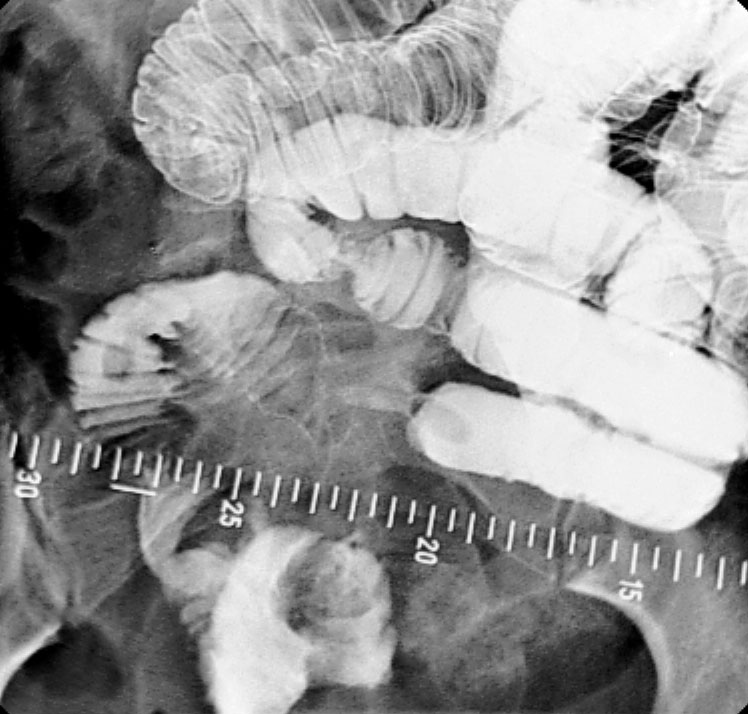

소장 조영술은 소장의 전체적인 형태와 병변을 확인하는 검사다. 바륨 추적 검사는 소장을 연구하는 데 사용된다.[1]바륨은 경구 투여하며, 때로는 디아트리조산(Gastrografin)과 혼합하여 장 통과 시간을 줄인다. 정맥 내 메토클로프라미드를 혼합물에 첨가하여 위 배출을 촉진하기도 한다.[20] 바륨 식사 후 600ml의 0.5% 메틸셀룰로스를 경구 투여하여 바륨이 소장을 통과하는 데 걸리는 시간을 줄이고, 조영제로 채워진 소장의 투명도를 높여 소장 추적 검사 영상을 개선할 수 있다.[17] 장 통과 시간을 줄이는 다른 방법으로는 바륨 식염수 혼합물 투여 후 얼음처럼 차가운 생리 식염수를 추가하거나[18] 건조한 식사를 제공하는 것이다.[19]

이후 20~30분 간격으로 앙와위 자세에서 X선 촬영을 한다. 실시간 투시경 검사를 사용하여 장 운동성을 평가한다. 영상 촬영 중에는 방사선 전문의가 장 루프를 분리하기 위해 복부를 누르거나 촉진할 수 있다. 검사에 필요한 총 시간은 장 운동성 또는 통과 시간에 따라 다르며 1~3시간 사이로 변동될 수 있다.[20]

소장 추적 검사의 경우, 바륨을 경구 투여하며, 때로는 디아트리조산(Gastrografin)과 혼합하여 장 통과 시간을 줄인다. 정맥 내 메토클로프라미드를 혼합물에 첨가하여 위 배출을 촉진하기도 한다.[20] 20~30분 간격으로 앙와위 자세에서 X선 촬영을 하며, 실시간 투시경 검사를 사용하여 장 운동성을 평가한다. 검사에 필요한 총 시간은 장 운동성 또는 통과 시간에 따라 다르며 1~3시간 사이로 변동될 수 있다.[20]